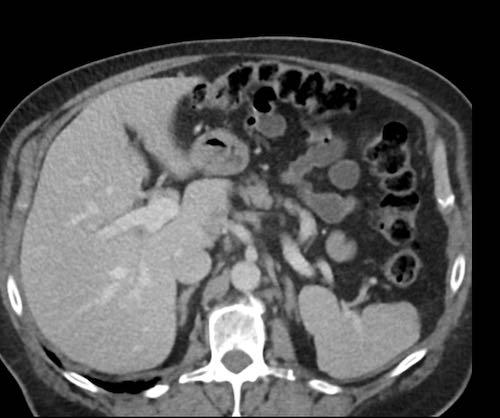

Cơ hoành

Do tác động của hô hấp, các tế bào khối u tự do bị hút vào mặt bụng của cơ hoành.

Các nốt cấy ghép này thường bị đánh giá thấp hoặc bỏ sót trên các lát cắt axial và được ghi nhận rõ hơn nhiều trên các mặt phẳng coronal hoặc sagittal.

Trong trường hợp này, các nốt khối u hiện diện rõ ràng và bao phủ phúc mạc gan.